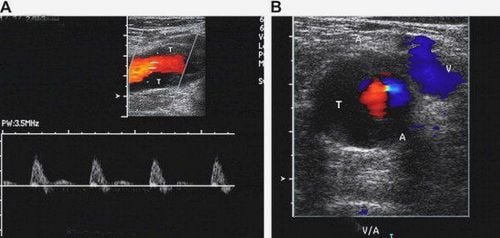

Hình ảnh siêu âm Doppler có thể giúp các bác sỹ quan sát và đánh giá:

- Sự tắc nghẽn lưu lượng máu do xuất hiện cục máu đông

- Khối u hoặc các dị tật mạch máu bẩm sinh

- Đánh giá lưu lượng máu cung cấp đến các cơ quan khác nhau như tinh hoàn đối với nam hoặc buồng trứng đối với nữ. Tăng lưu lượng máu bất thường có thể là dấu hiệu của nhiễm trùng

- Đầu dò sẽ được các kỹ thuật viên nhẹ nhàng di chuyển trên da. Khi các đầu dò tiếp xúc với da, chúng gửi đi xung sóng âm tần số cao, sóng âm tiếp xúc với các cơ quan và nội tạng trong cơ thể rồi phản xạ ngược trở lại, các đầu dò có nhiệm vụ thu nhận hết âm phản xạ này, gửi cho bộ xử lý trung tâm. Tại đây, dựa vào cường độ sóng, thời gian âm phản xạ trở lại máy sẽ phân tích và đưa ra hình ảnh của các cơ quan, nội tạng đó được hiển thị trên màn hình. Đối với siêu âm Doppler, sự chuyển động của các tế bào máu gây ra sự thay đổi của cường độ sóng phản xạ qua đó hiển thị hình ảnh dòng máu chảy trong lòng mạch